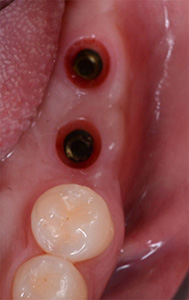

インプラントの被せ物はネジで装着、必要時は取り外し可能となります。

最終的にネジ穴は、白い樹脂で封鎖します。

上のネジ穴の写真やレントゲン画像から、インプラントが計画通りに埋入されて良好に終了していることが確認できます。